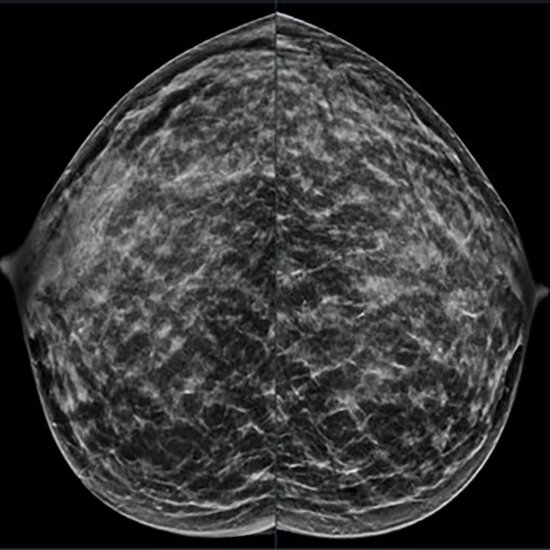

News • Appeal for earlier screening approaches

Breast cancer – including aggressive variants – are surprisingly common in younger women, a new study shows. The findings strengthen the case for earlier, risk-tailored screening, the authors say. |